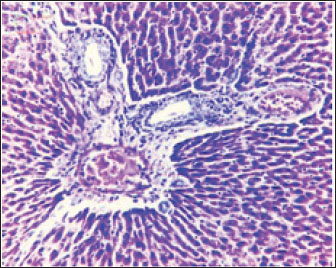

The histopathological results in the TCE group showed that the treatment with TCE for 90 days ( 110 LD50daily) resulted in the infiltration of inflammatory cells, mainly lymphocytes, in portal area with mild fibrosis, hyperplasia of the bile duct (Fig. 3) showed congested central vein, proliferation of Kupffer cells, apoptotic cells and, with dilated sinusoids, while the (Fig. 4) showed severe fatty changes of hepatocytes in the form of cytoplasmic lipid droplets (microvascular steatosis) with proliferation of Kupffer cells. (Fig. 5) showed degenerative changes with necrosis of hepatocytes with proliferation also (Fig. 6). Histopathological section of the liver (group + with oil) showing mild degenerative changes of hepatocytes. In Fig. 7, the histopathological section of the liver (c +group/90 days) showing mild degenerative changes of hepatocytes with few inflammatory cells infiltration (Fig. 8). Finally, in Fig. 9, histological section of the liver (control group) with normal structure.

Fig. 3. Histopathological section of the liver (TCE group/90 days) showing infiltration of inflammatory cells, mainly lymphocytes, in the portal area with mild fibrosis and hyperplasia of the bile duct (H&E stain 100X).